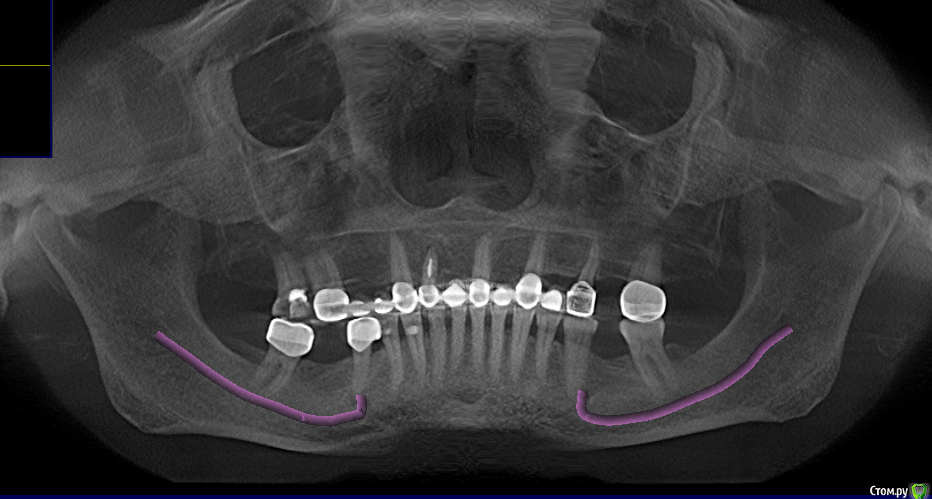

Большой Зеленый Опубликовано 6 мая, 2016 Поделиться Опубликовано 6 мая, 2016 Дайте нормальную ортопантомограму 2 Ссылка на комментарий

togrul Опубликовано 6 мая, 2016 Автор Поделиться Опубликовано 6 мая, 2016 Панорамный снимок Ссылка на комментарий

pit Опубликовано 6 мая, 2016 Поделиться Опубликовано 6 мая, 2016 В плане лечения у паца 2 варианта 2 протяженных моста и 2 коронки на имплантатах или подкова. Линия улыбки, наверное, закрытая. Если да, то без разницы какой из вариантов будет выбран.Если линия улыбки открытая, то с точки зрения эстетики, если не отработать с десной в области 14,12,11,22, 24 зубов оба варианта будут не очень.Еще один важный момент, в случае использования имплантатов (имплантата и консоли) с одной стороны и протяженного мостовидного протеза с другой разрыв конструкции придется на область 11 и 21 зубов. Есть вероятность, что спустя некоторое время между зубами 11 и 21 образуется щель.Учитывая вышеперечисленное, я бы склонился в данном случае к подкове и беседовал бы с пацем в пользу выбора более качественного материала конструкции. Ссылка на комментарий

pit Опубликовано 6 мая, 2016 Поделиться Опубликовано 6 мая, 2016 Если же говорить только об имплантах, то 1 и консоль будет смотреться лучше. Так как высота сосочка между имплантом и понтиком всегда выше, чем между имплантом и имплантом. Разумеется при правильной моделировке понтика. Но для консольной конструкции я бы предпочел диаметр винта 4,3 и винтовую фиксацию, что в данном случае повлечет за собой приличный объем пластики.Если же линия улыбки закрытая, то 2 импланта. В позицию 12зуба - 3,5, а в позицию 11зуба - 3,0 и минимальный объем пластики. Ссылка на комментарий